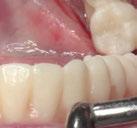

(Figuras 22 y 23). Se realiza fresado transgingival mínimamente invasivo y guiado hasta la inserción de los implantes, siguiendo el protocolo preestablecido e indicado (Figuras 24 a 26).

Durante la colocación de los implantes comprobamos una inserción con torque superior a 35 N/cm2

Retiramos la férula y comprobamos una correcta estabilidad primaria mediante mediación de valores

ISQ favorables en la mayoría de los implantes. Seguidamente se extraen los dientes remanentes que han actuado de medio retentivo para la férula quirúrgica.

Dentro de la fase quirúrgica propiamente dicha, una vez terminada la inserción de los implantes y

comprobada su estabilidad primaria, colocamos pilares transepiteliales

Multiplus para registrar una impresión digital mediante escaneado sobre ellos (Figuras 27 a 29)